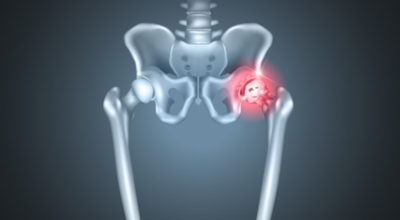

각별히 젊은 남성에게 잘 발생하며 엉덩이와 골반 주위에 뻐근한 통증이 동반되며 정상적인 보행이 되지 않고 절뚝거리는 증상이 나타난다면 대퇴골두 무혈성 괴사일 가능성이 있답니다. 이 증상은 괴사 부위의 골절이 발생되어 고관절 손상으로 이어지면 발생하는 증상으로 아직까지 정확한 원인은 규명하기 힘드나 과음이나 고지혈증, 스테로이드 과남용이 영향을 줄 수 있어요.

3. 고관절 통증 증상 - 엉덩이 통증